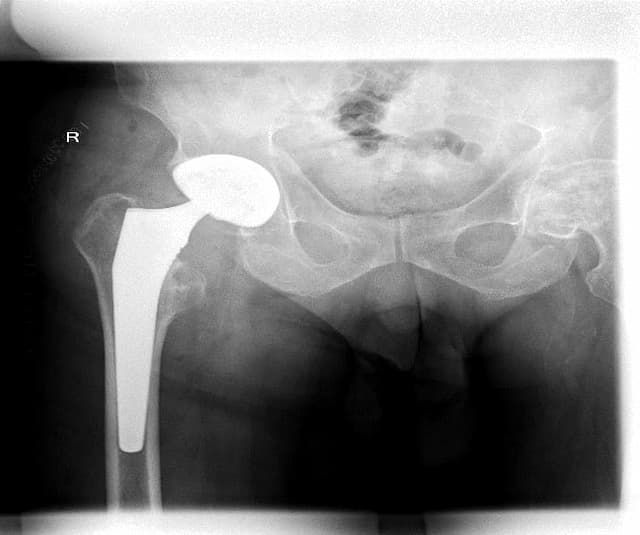

Мэс заслын өмнөх болон дараах зурагууд

Түнхний үе хагас солих мэс засал (Bipolar Hip QRL) image1Түнхний үе хагас солих мэс засал (Bipolar Hip QRL) image2